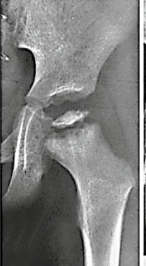

Q

This shows

osgood-schlatter

blounts disease

SUFE

Perthes

CDH

A

the arrow is pointing to:

osgood schlatter